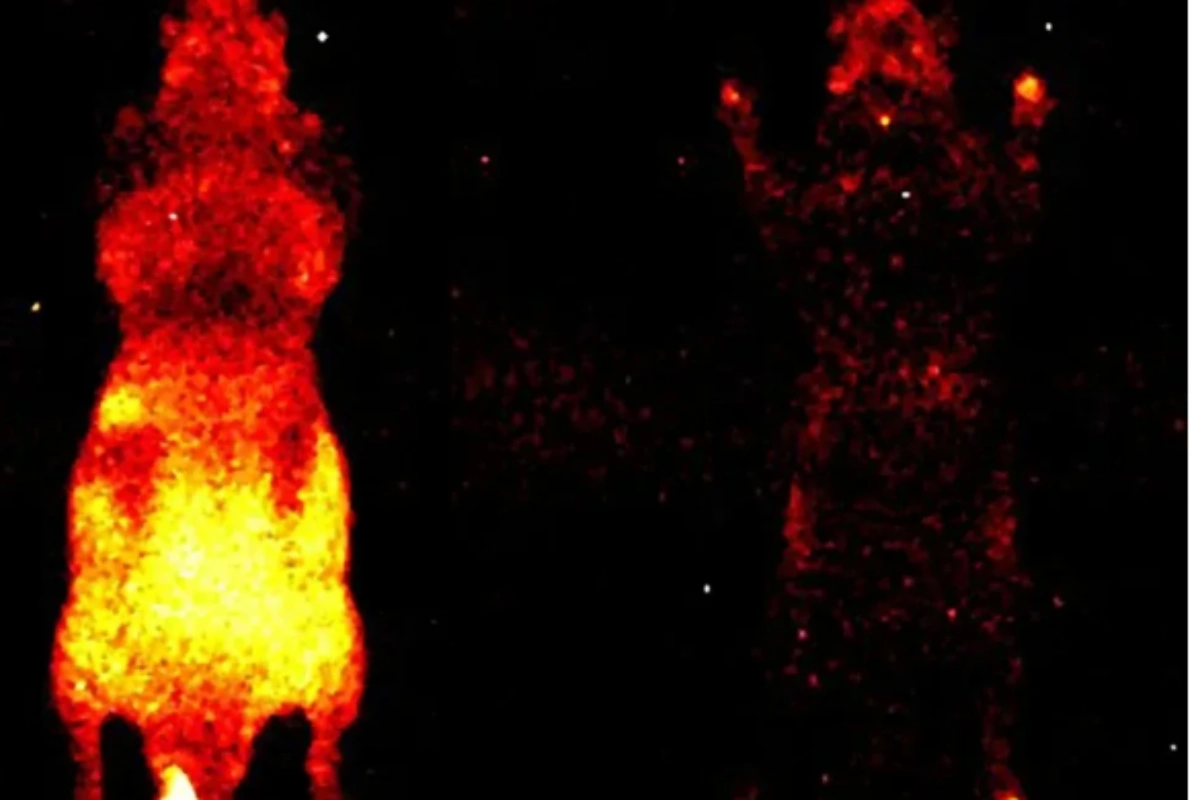

Əvvəlki tədqiqatlarda foton emissiyası yalnız ayrı-ayrı hüceyrələr səviyyəsində müşahidə olunmuşdu. Lakin Kalqari Universitetindən dosent Daniel Oblakın rəhbərlik etdiyi qrup bütün orqanizm səviyyəsində - həm canlı, həm də ölü vəziyyətdə - bu parıltını qeydə almağa nail olub.

Tədqiqat üçün siçanlar xüsusi qaranlıq kameraya yerləşdirilib və iki saatlıq eksperiment zamanı canlı heyvanların bədəni boyunca yayılan zəif işıq, baş, daxili orqanlar və pəncələrdə "isti nöqtələr" şəklində qeydə alınıb. Alimlər hesab edirlər ki, gələcəkdə bu zəif parıltının monitorinqi travmaların və müxtəlif xəstəliklərin erkən diaqnostikası üçün istifadə oluna bilər.